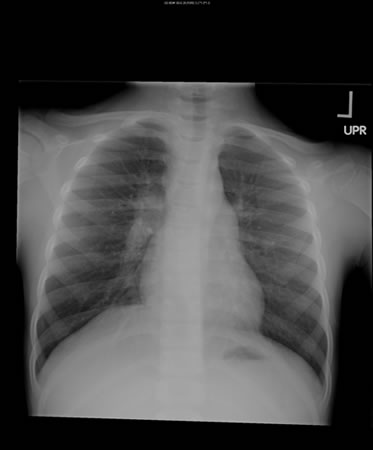

[Figure caption and citation for the preceding image starts]: Right hilar adenopathy in a childFrom the personal collection of David Horne and Masahiro Narita; used with permission [Citation ends].